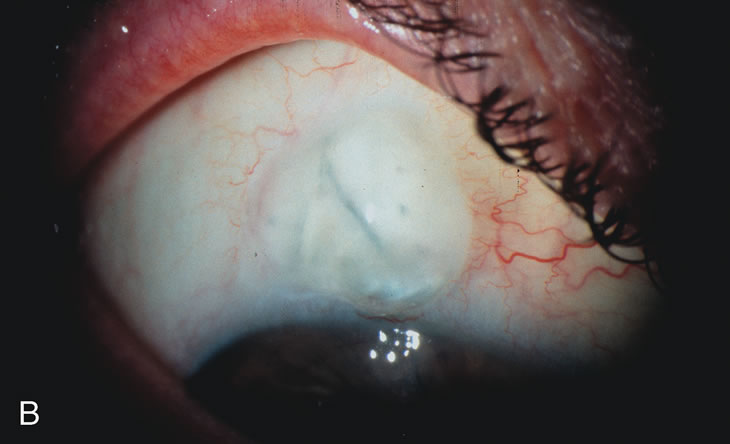

Fig. 3. Partial bleb failure following clear corneal phacoemulsification with foldable IOL. A. Preoperative bleb appearance prior to temporal lens extraction. Preoperative IOP was 12 mm Hg on no antiglaucoma medications. Time from 5-FU trabeculectomy surgery to lens extraction was one year. B. Bleb appearance 2 months after clear corneal cataract surgery with topical anesthesia. Following lens extraction, increased vascularity was noted along with decreased size of the filtering bleb. IOP increased to 20 mm Hg as early as 2 weeks after surgery, necessitating topical antiglaucoma therapy. C. High magnification view of bleb before lens extraction demonstrates diffuse pale bleb. D. High magnification view of bleb 2 months after surgery. There are vessels surrounding the nasal side of the bleb and the overall bleb size is smaller.